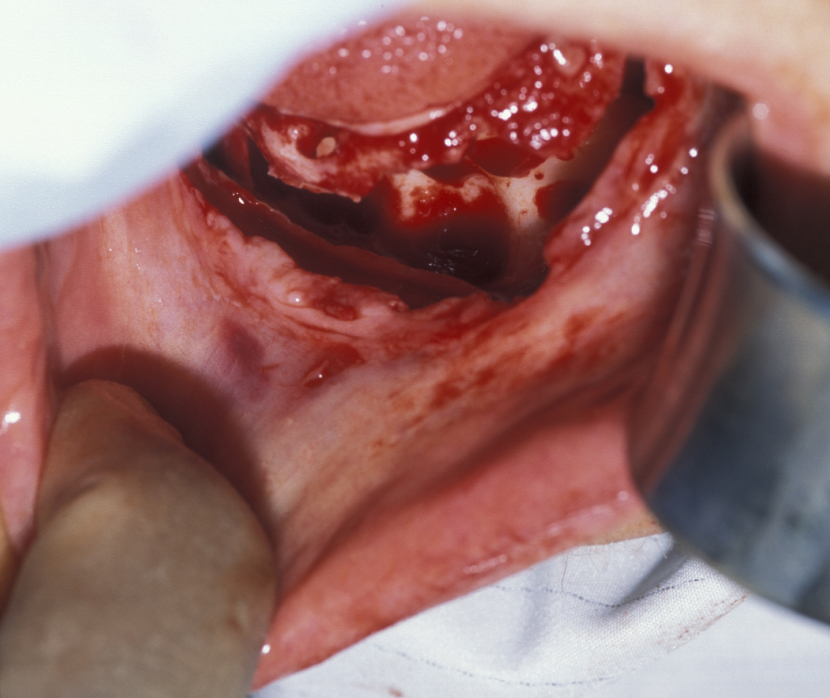

Figure 11: Approach to a large recurrent keratocyst that has grossly distorted the buccal cortex (outward facing cover of mandibular bone).

Figure 12: The involved bone is removed, thus exposing the cyst.

Figure 13: The thick-walled cyst is removed and the surrounding bone is excised.